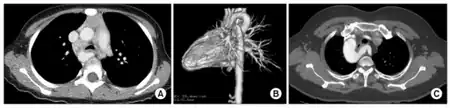

Infants with vascular rings typically present before 12 months with respiratory or esophageal symptoms like stridor, wheezing, cough, dysphagia, or difficulty feeding. The stridor improves with neck extension, differentiating from laryngomalacia which is relieved by prone or upright positioning, and will not be relieved with corticosteroids or epinephrine, unlike croup. Diagnosis requires a high degree of clinical suspicion and can be confirmed with barium contrast esophagogram for those with esophageal symptoms, bronchoscopy, or CT or MRI.[3]